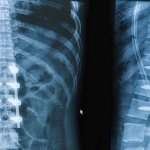

In addition, infection of the fetus in the first trimester, when the laying and beginning of organ development occurs, may cause the formation of encephalitis, combined with microcephaly (underdevelopment of the brain) and hydrocephalus (dropsy of the brain), the development of anomalies of the digestive organs, malformations of the heart and vessels, etc.

The 2nd and third trimesters are also dangerous due to spontaneous abortion, intrauterine death, malnutrition, anemia and sepsis in the fetus, the development of hemorrhagic syndrome with bleeding and thrombosis, meningoencephalitis, epilepsy, cerebral necrosis, pneumonia, damage to the eyes, hearing aid, skin, mucous membrane oral cavity, liver damage with the development of jaundice, etc.